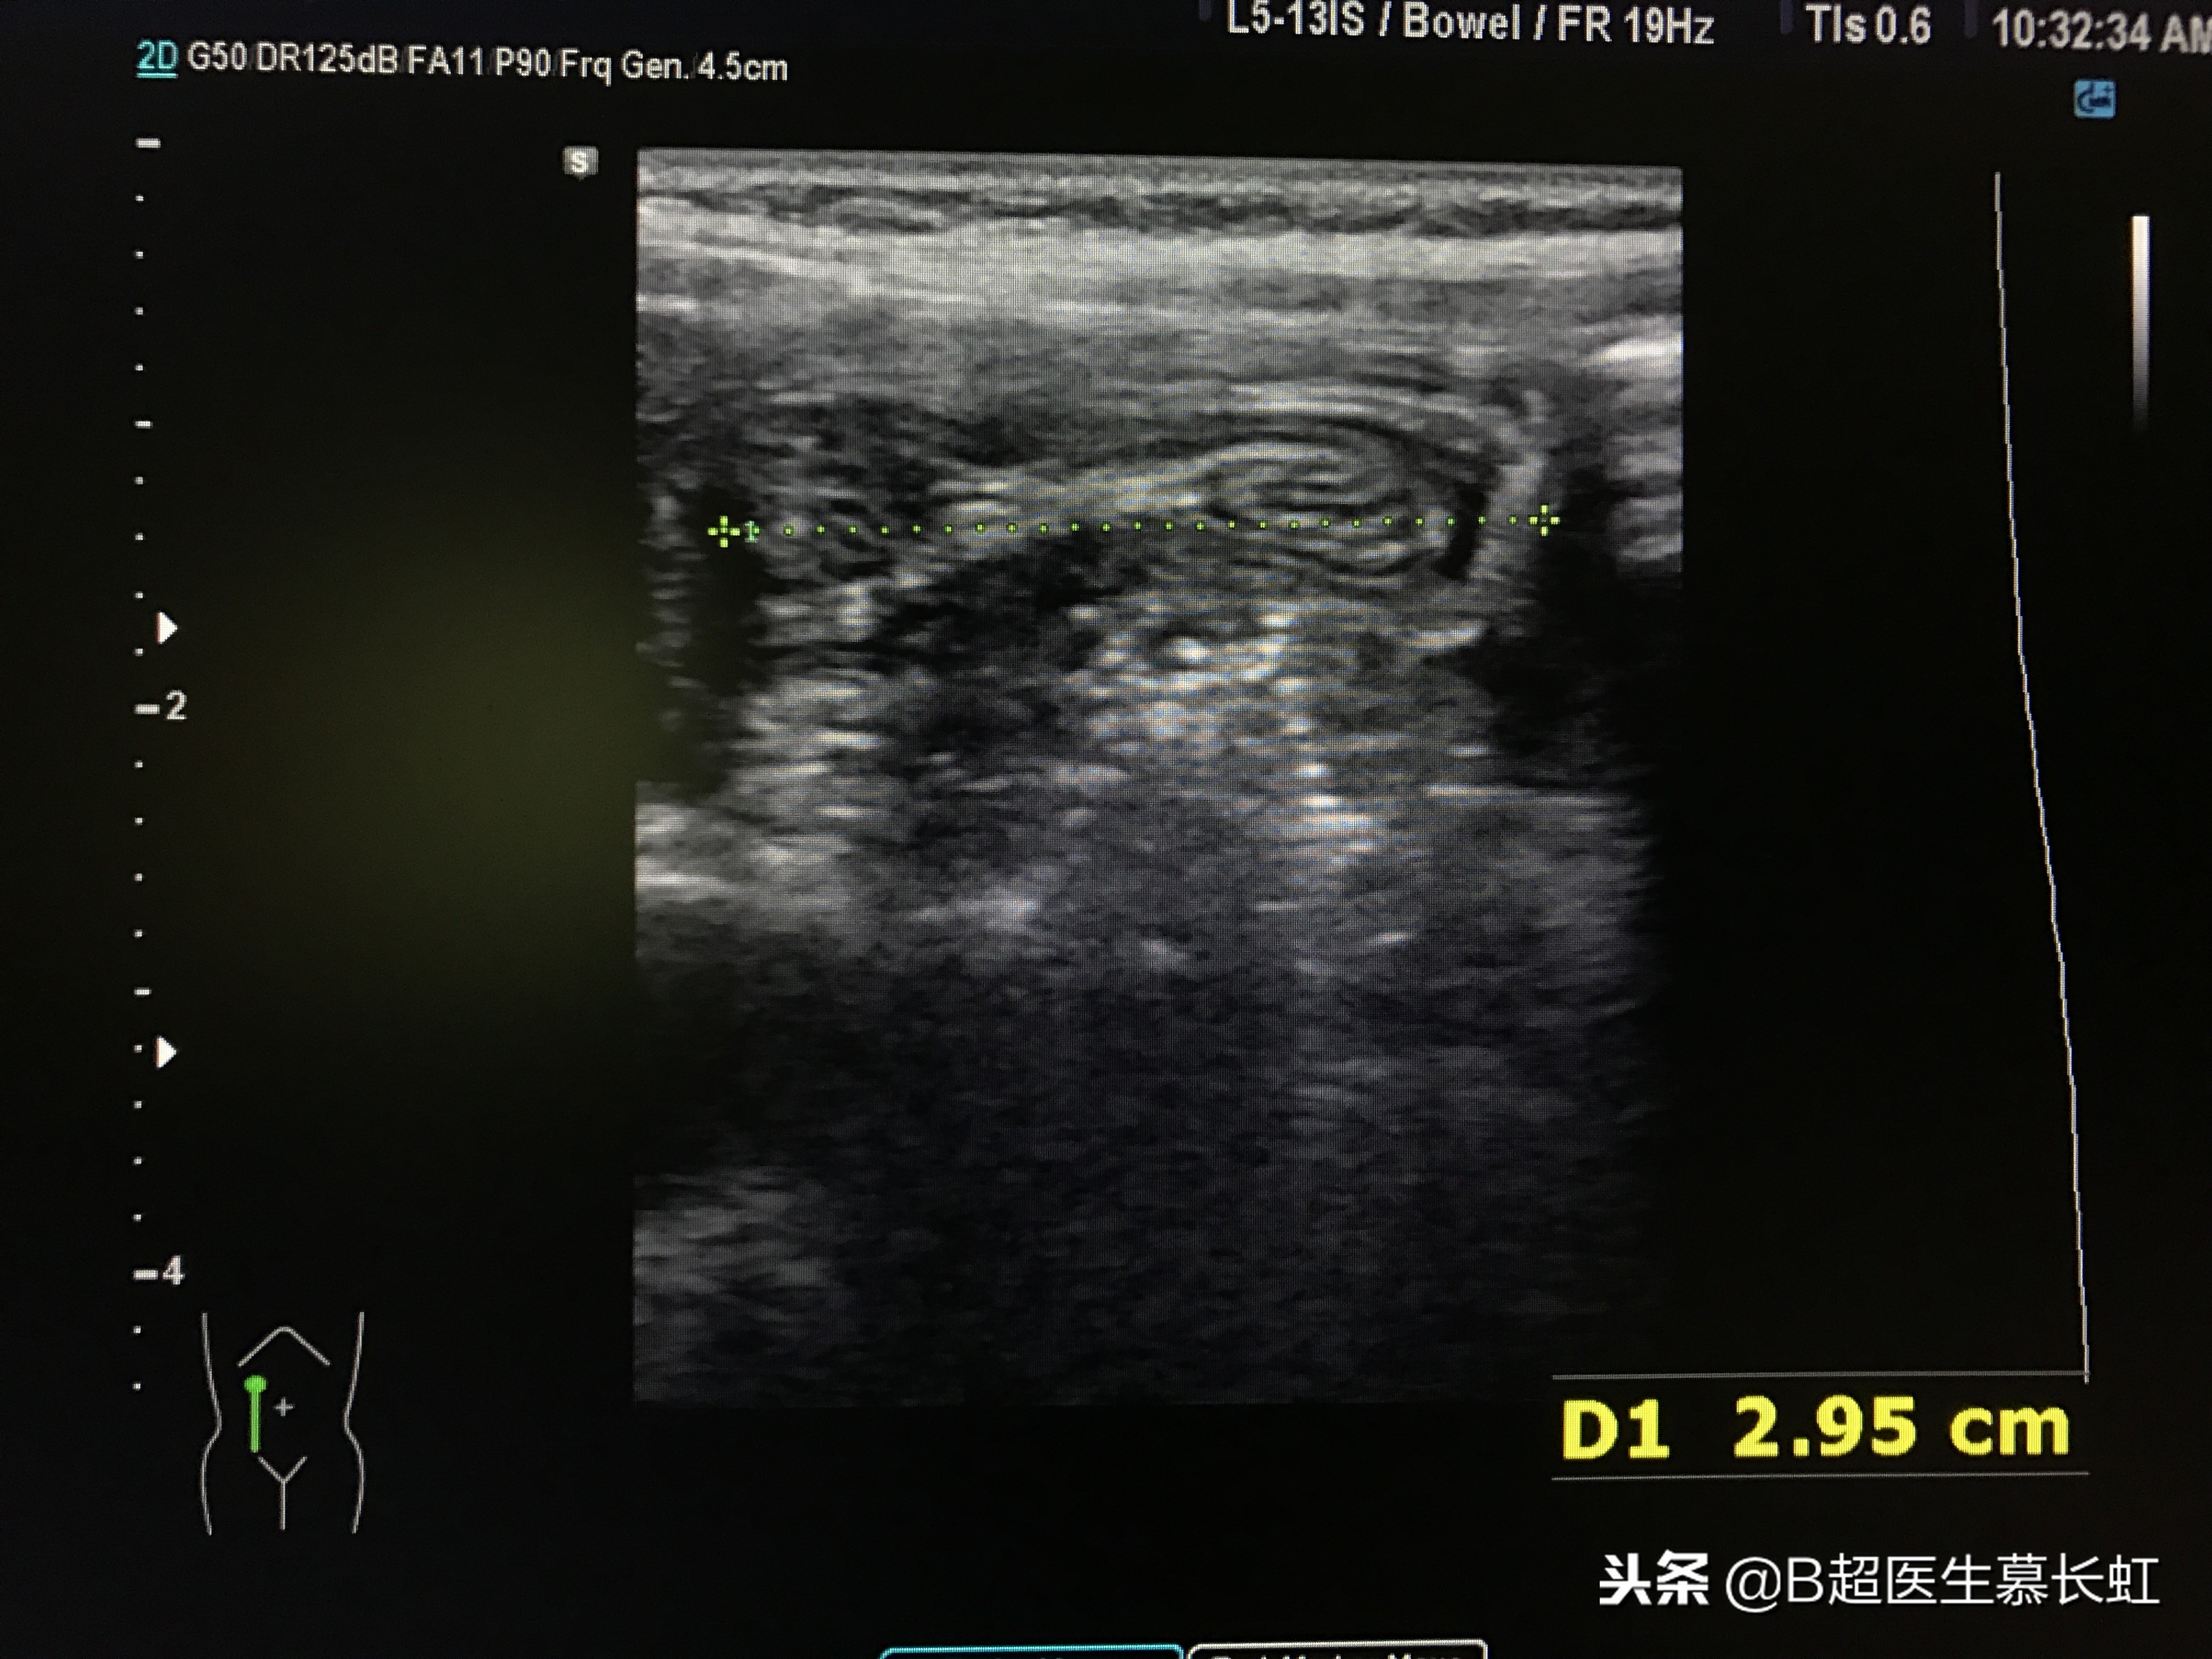

但给这四个小朋友做超声检查,扫查腹部时,均在脐周发现肠套叠。

超声表现:1、同心圆征:肠壁水肿不严重。

2、炸面圈征:外层肠壁水肿增厚。

3、炸面圈内新月征:内部有套入肠系膜。

同心圆征,两处肠套叠